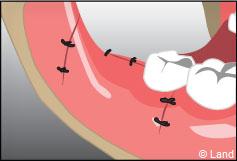

L’intervention commence là aussi par une anesthésie locale, puis le chirurgien-dentiste procède à une incision de la gencive et à un dégagement du tissu osseux autour de la dent.

Parfois cette dernière est sectionnée pour ne pas traumatiser l’os souvent responsable de suites opératoires douloureuses.

Une fois la dent enlevée, la cavité est nettoyée. En cas d’une dent souffrant d’inflammation, le tissu infecté sera également enlevé.

La fermeture de la cavité s’effectue souvent à l’aide de points de suture servant à réunir les bords de la gencive.